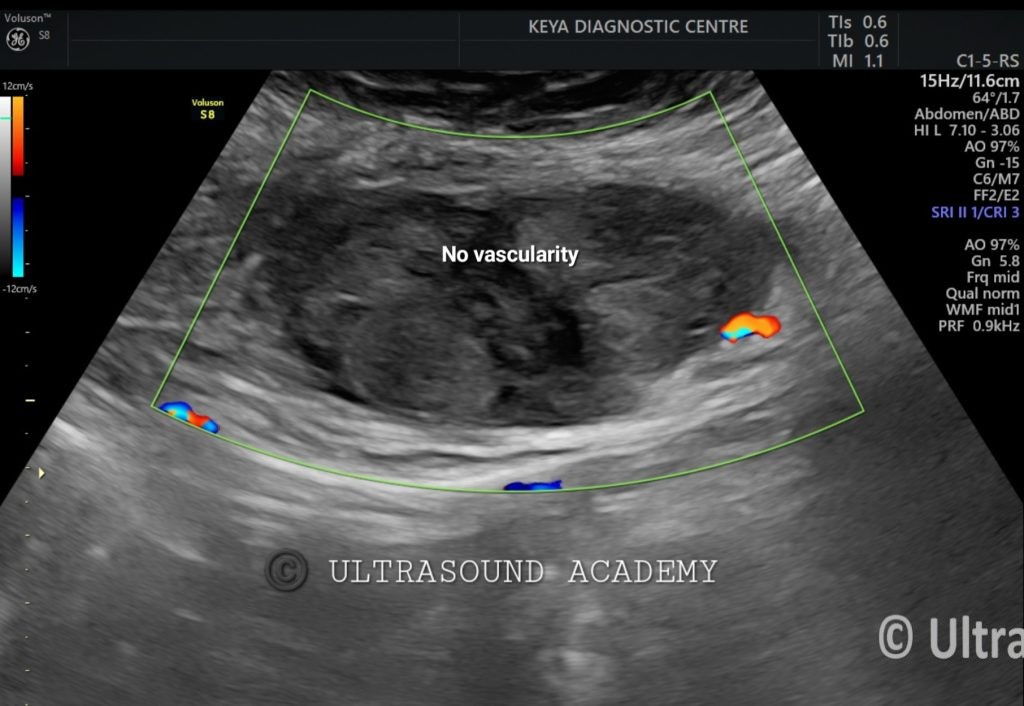

On B mode ultrasound:

There is well defined heterogenous predominantly hyperechoic lesion/ area is seen involving the left rectus abdominis muscle. No intra- abdominal extension is noted.

On Color Doppler examination: No vascularity noted.

So, the diagnosis of acute rectus abdominis muscle hematoma is given.

Doppler Ultrasound Features:

• No significant internal vascularity (distinguishes hematoma from tumors).